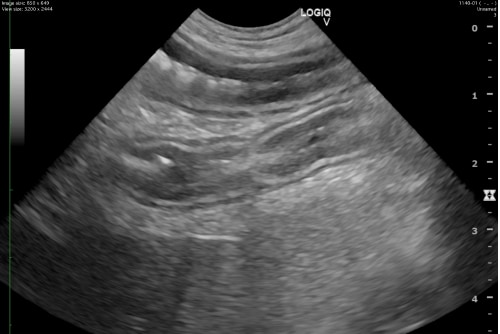

血液検査および超音波検査から急性膵炎だと診断。静脈輸液、内科治療により症状が改善しました。

解説

犬の急性膵炎は、膵臓の炎症が急激に進行する病気です。明確な原因は判明していませんが、高脂血症や一部犬種などでは脂肪分の多い食事が発症リスクをあげることがわかっています。症状には嘔吐、下痢、腹痛、食欲不振、脱水が含まれます。これら臨床症状に加え、血液検査、画像診断を総合的に診て診断します。治療は、支持療法が主となります。例としては点滴による水分補給、痛みの管理、炎症の抑制を中心に行います。重症の場合、治療が遅れると、慢性膵炎へ移行や、最悪の場合死亡することもある恐ろしい病気です。早期の発見と適切な治療が予後を改善します。